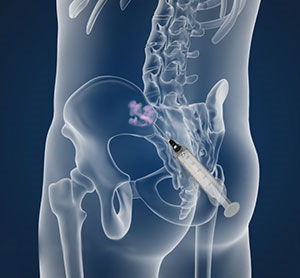

Sacroiliac joint (SIJ) pain is a common source of lumbosacral back pain that we can diagnose and treat with 2 types of fluoroscopically guided procedures:

- Sacroiliac joint steroid injections or

- Blocks of nerves to the SIJ with local anesthetic (for diagnosis) twice to determine if blocking long term with Radiofrequency Ablation/RFA (for treatment) is recommended.

Treatment with RFA tends to last around 9 months on average (give or take 3 months), which could be 2-4 times longer than the SIJ steroid injection. However, the steroid injection requires just one session that combines diagnosis and treatment, where the RFA procedure typically requires 3-4 sessions initially. If successful, future treatments with RFA can be repeated generally without the preliminary diagnostic blocks for recurrence of the same pain.

Depiction of a left sacroiliac joint injection